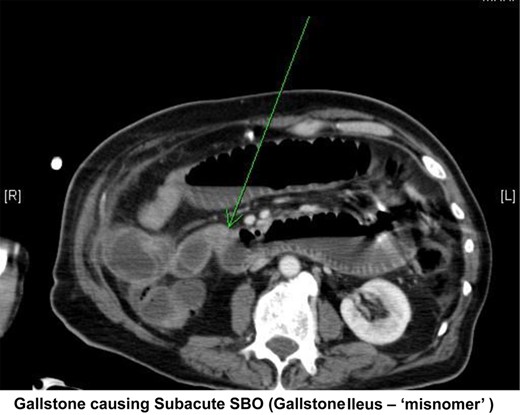

Small bowel obstruction with transition in the distal ileum probably due to obstructing gallstone (Fig. 2).

Transverse section from abdominal CT showing a small bowel obstruction with arrow indicating an intraluminal gallstone.

Given the paucity of information elicited from the patient in terms of history, the differential diagnoses were based on the results of the CT scan. The patient has small bowel obstruction the causes of which appeared to be either secondary to inguinal hernia or gallstone ileus. The treatment of which is very different, hernia being treated with an inguinal repair and gallstone ileus being treated with either laparoscopic resection or laparotomy. The decision was made to proceed to laparotomy on the basis that if the obstruction was secondary to hernia, a resection may well need to be performed, the same approach would also allow the resection for gallstone ileus. In addition, gallstone ileus was felt to be the more likely diagnosis given the presence of pneumobilia.

As a result of the site of obstruction being the same, it is not uncommon for gallstone ileus and caecal mass to be confused prior to surgery. The main distinguishing features of gallstone ileus over caecal mass are small bowel obstruction with the presence of pneumobilia and a gallstone in the right iliac fossa on X-ray/CT, referred to as Rigler's Triad [3].

This case has all the features of Rigler's triad suggestive of gallstone ileus, but the intraluminal gallstone proved to be incidental with the stone moving freely within the lumen. The cause of the obstruction was the caecal tumour, which was not evident on preoperative imaging. There have been no previously reported cases of concurrent gallstone ileus and caecal tumour in the literature.